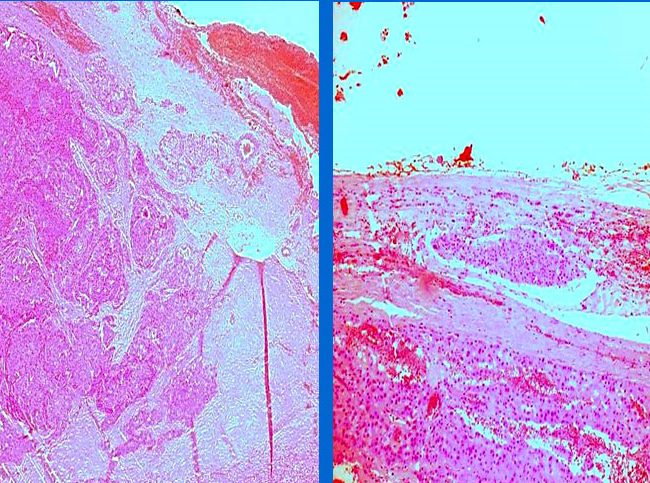

Carcinoma anaplásico de tiroides, originado en un carcinoma de células de Hurtle

Autores: Dr. Lucas Moretti, Dr. Boris Elsner. Centro de Patología. C.A.B.A Reseña: Paciente de sexo femenino de 82 años, que consulta por bocio de crecimiento progresivo,...